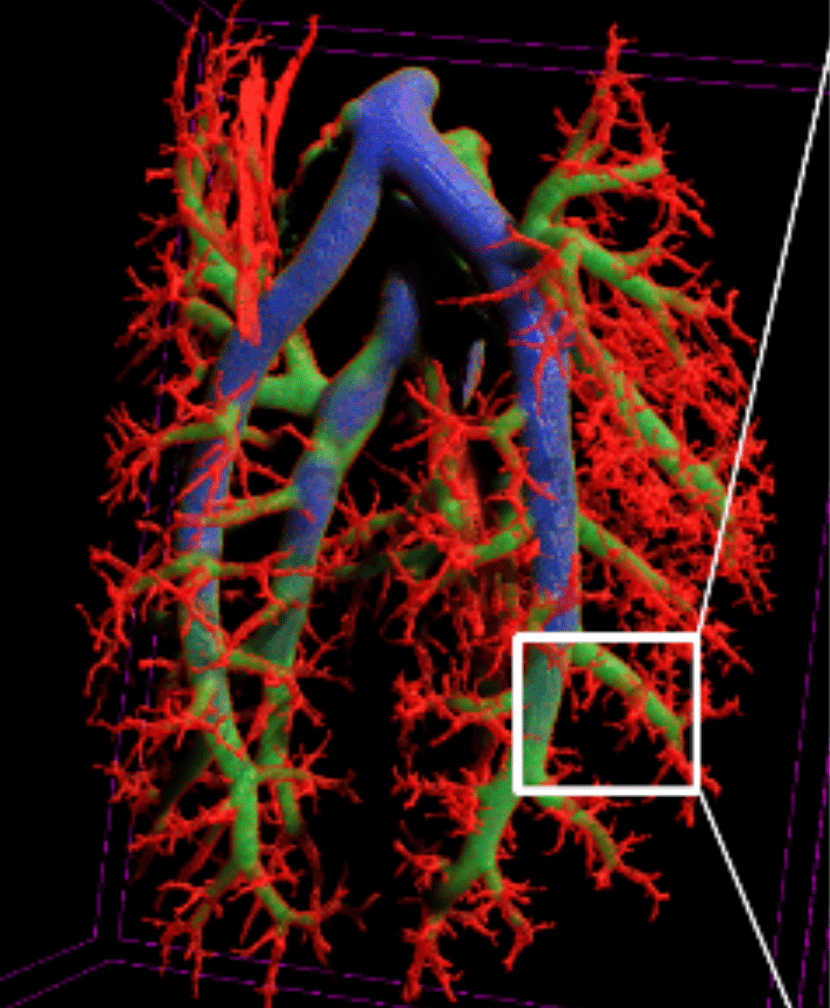

Gain access to a library of method notes built up over two decades. Extract more information from a micro-CT through the uses of contrast agents and tissue preparation protocols: perfused vasculature for vessel thickness, heavy metal stains (iodine [Lugal’s], phosphotungstic acid (PTA), osmium tetroxide) for tissue differentiation, gold colloids for time-resolved cardiac gating, chemical drying for high resolution imaging, or make use of post-acquisition tools for time-resolved lung and cardiac imaging.

Ex-vivo high resolution lung imaging

High resolution micro-CT provides a 3D solution for measuring the morphometric parameters of lung parenchyma. Through the use of chemical drying of specimens to enhance contrast and stabilize samples, it is possible to image lung tissue at high resolution, typically around 1μm pixel size or less. At this resolution, the alveolar membranes can be visualized and parameters such as mean cord length and mean linear intercept that are acquired through standard light-microscopy images in 2D can now be calculated in 3D. This provides the obvious advantage that the results are no longer biased by the cross section that is chosen and analyzed. Full 3D integration of the data is now possible.